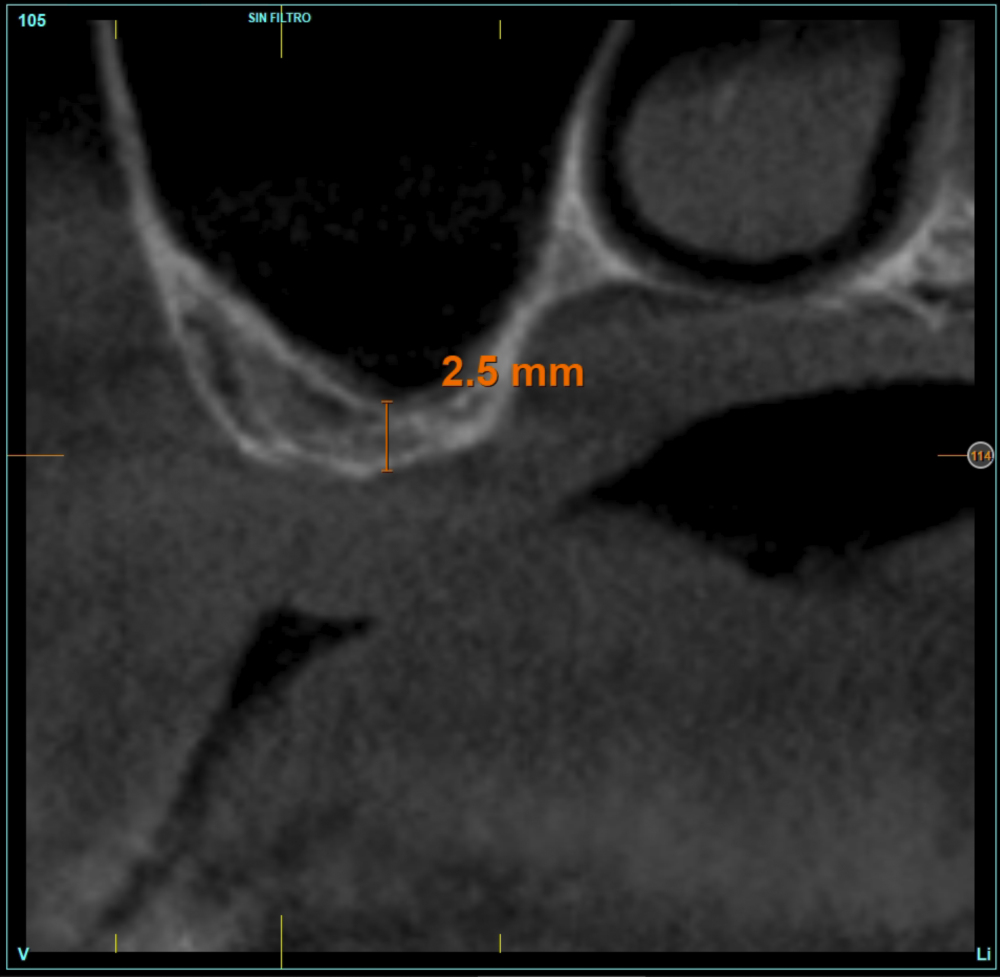

Material and method. A retrospective study has been carried out in patients in whom extra-short implants (4.5 and 5.5 mm length) were inserted directly by transcrestal elevation with residual ridges between 2 and 3 mm. The implant was the analysis unit for the descriptive statistics regarding location, implant dimensions, and radiographic measurements. The patient was the measurement unit for the analysis of age, sex and medical history. The main variable was the gain in height over the apex of the implant after 6 months of the surgery and one year after the load comparing both measurements and as secondary variables the biological complications and the implant failure were recorded.

Results. Ten patients who met the inclusion criteria were recruited and 20 implants were inserted. The mean residual bone volume height was 3.1 mm (+/- 0.3 mm with a range elevation above the apex of the implant in millimetres is of 2.8 mm (+/- 0.99 range 1.9 -5 mm). In the control cone-beam after one year of the studied load of the implants, the bone gain achieved was maintained, with no decrease in the volume gained, only three cases showed a decrease of between 0.4 and 0.5 mm of the initial volume at the end. No implants failed in the follow-up period and no biological complications were found in the surgery.